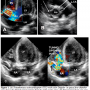

An 11-month-old female was referred by a pediatrician for evaluation of a continuous murmur. On examination, the child weighed 7.5 kg. Pulse was 106/min, collapsing in nature. Blood pressure was 100/20 mm Hg. There was a loud grade 4/6 ‘to and fro’ systolo-diastolic machinery murmur heard in the left-lower sternal border. Electrocardiogram (ECG) was normal. Chest radiograph showed cardiomegaly with apparent enlargement of the right atrium. Transthoracic real-time two-dimensional echocardiography (TTE) and color Doppler in apical five-chamber view showed dilated tunnel arising from the right aortic sinus (Figure 1A).

Parasternal short-axis view showed normal-sized left and right coronary arteries arising from left coronary sinus and large tunnel arising from right coronary sinus (Figure 1B). The TTE with color Doppler in the apical four-chamber view showed the tunnel opening into the RV (Figures 1C and 1D). Computed tomographic angiography (CT angio) revealed that the tunnel was arising above the right coronary sinus with both coronary arteries arising from a single left coronary ostium (Figure 2A). The tunnel was draining into the right ventricular infundibulum. (Figure 2B). The origin of the tunnel measured 8.5 mm and the distal RV end measured 6 mm.